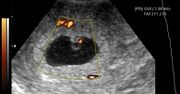

Płód w 6 tygodniu ciąży